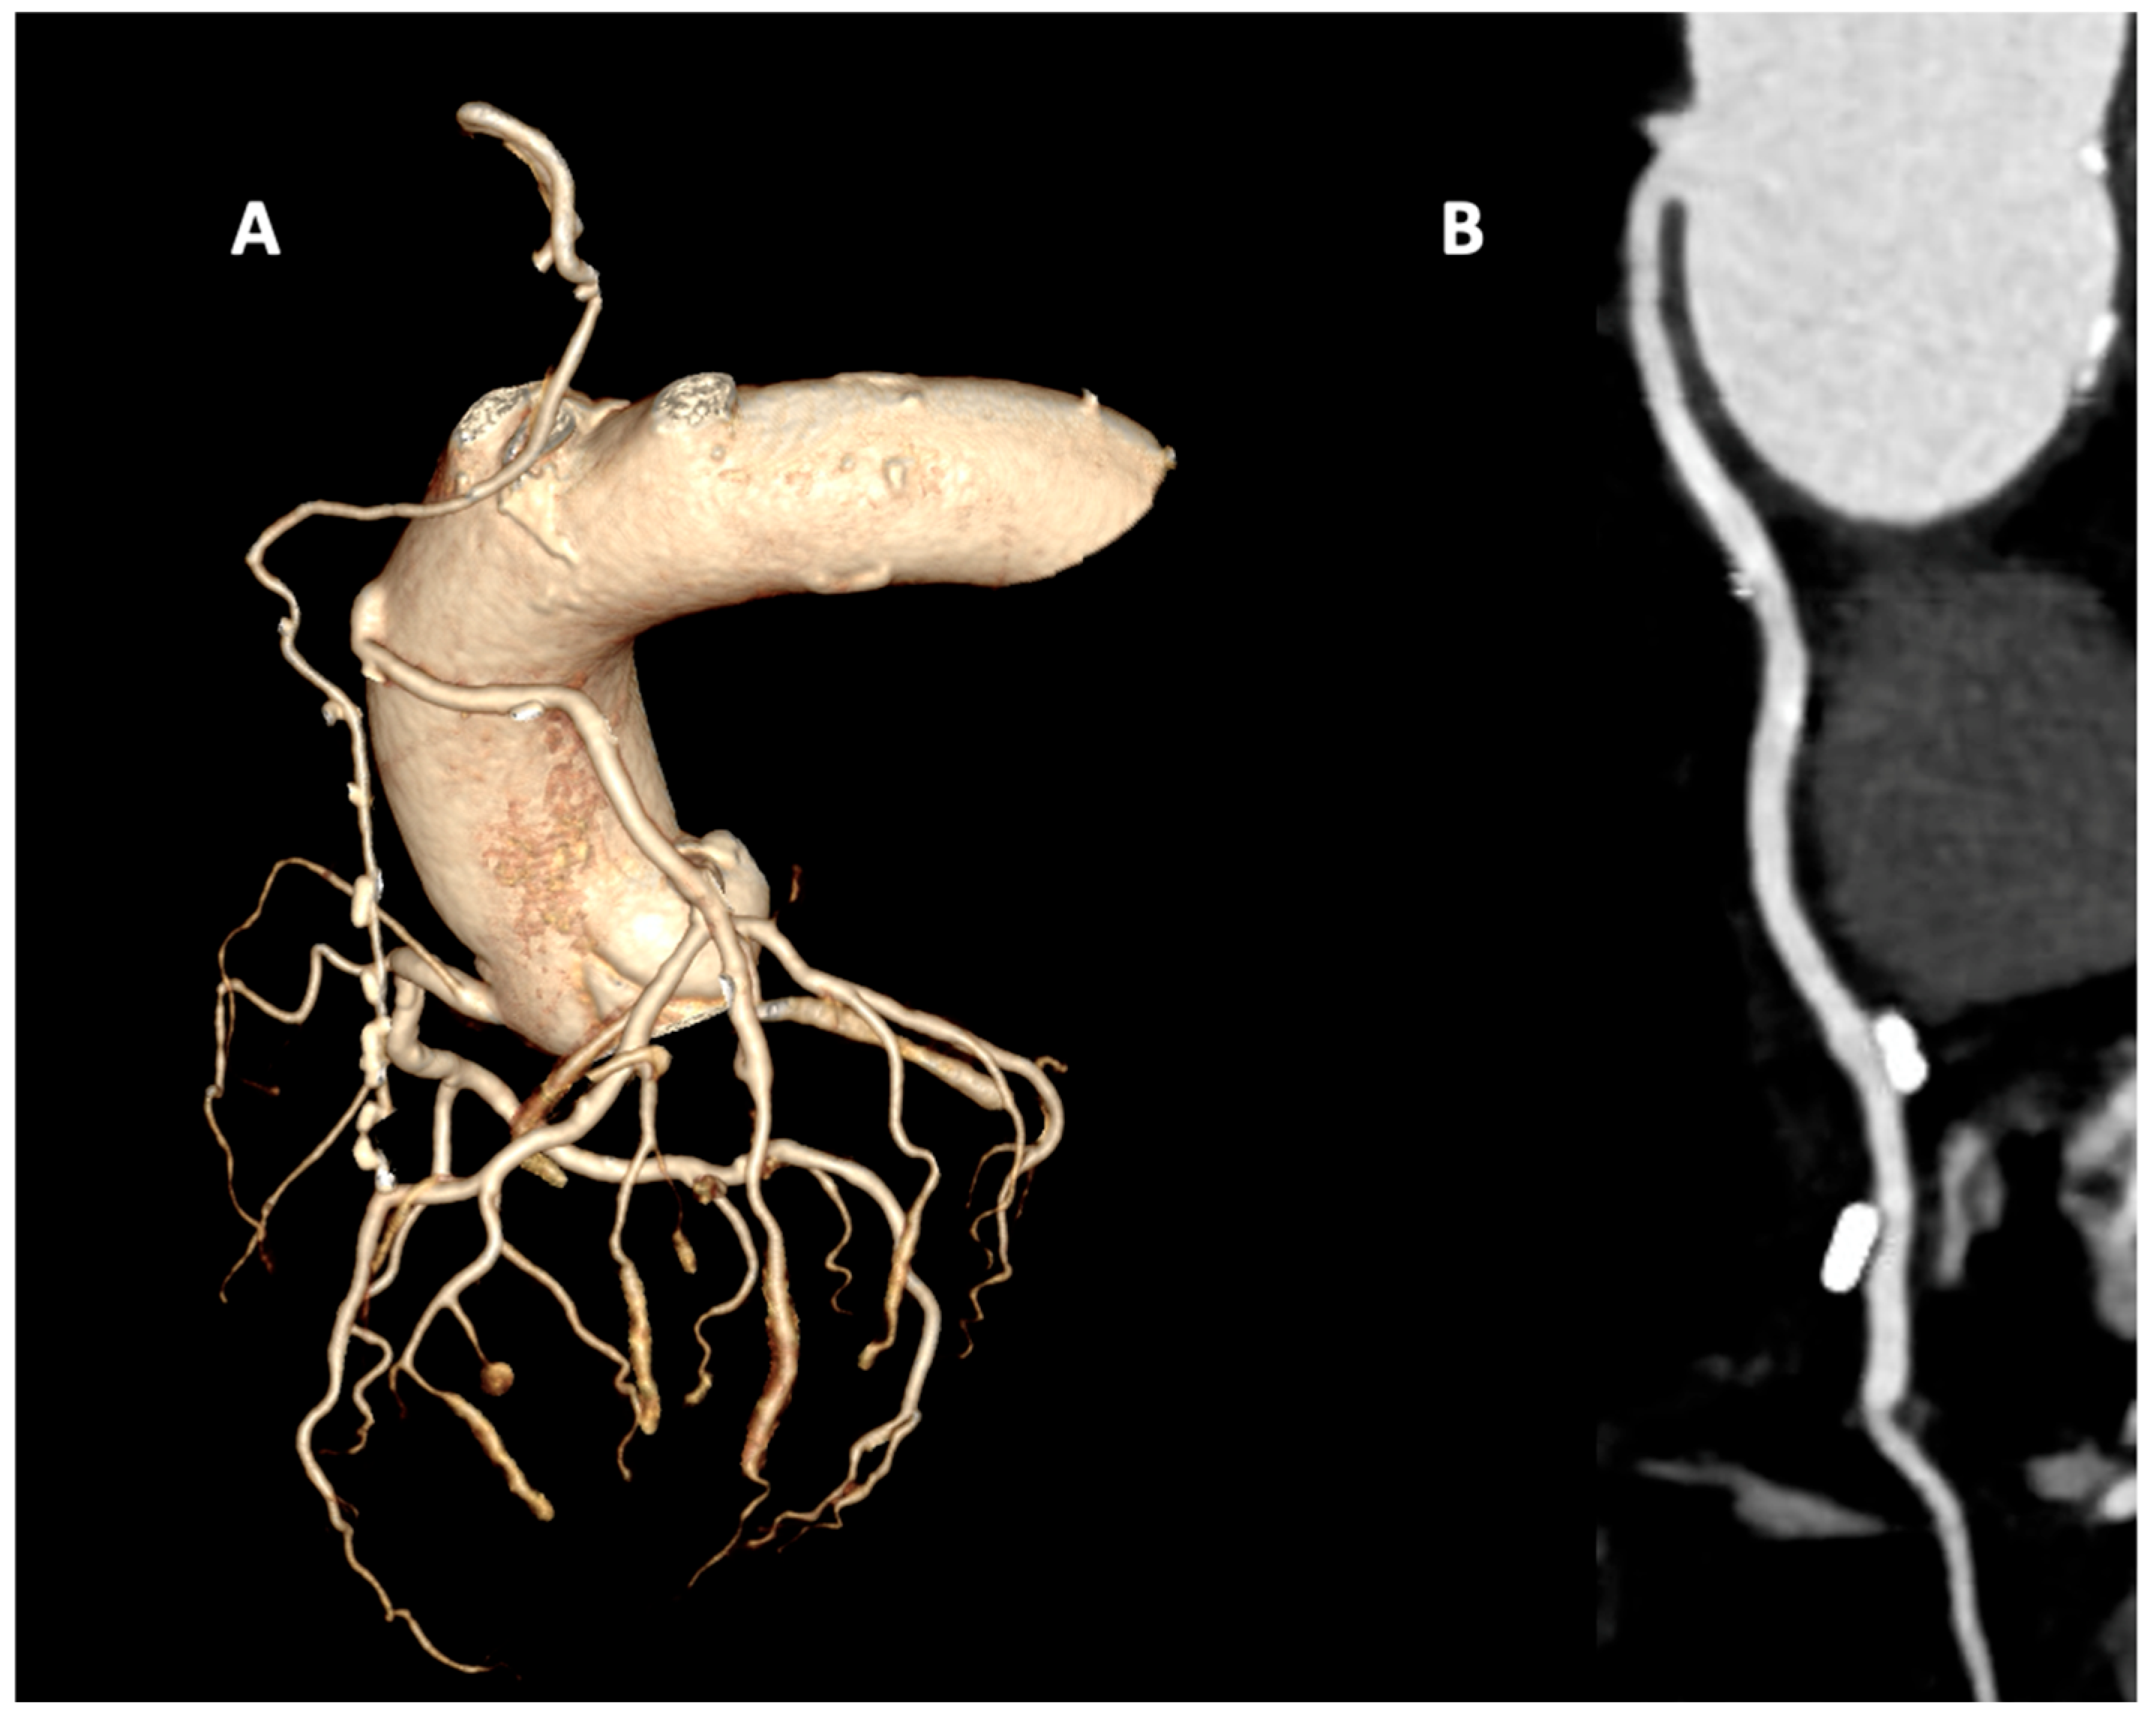

- Pesenti-Rossi, D.; Baron, N.; Georges, J.L.; Augusto, S.; Gibault-Genty, G.; Livarek, B. Assessment of coronary bypass graft patency by first-line multi-detector computed tomography. Ann. Cardiol. Angeiol. 2014, 63, 284–292. [Google Scholar] [CrossRef]

- Beirne, A.M.; Rathod, K.S.; Castle, E.; Andiapen, M.; Richards, A.; Bellin, A.; Hammond, V.; Godec, T.; Moon, J.C.; Davies, C.; et al. The BYPASS-CTCA study: The value of computed tomography cardiac angiography (CTCA) in improving patient-related outcomes in patients with previous bypass operation undergoing invasive coronary angiography: Study protocol of a randomised controlled trial. Ann. Transl. Med. 2021, 9, 1395. [Google Scholar] [CrossRef] [PubMed]

- Gabriel, J.; Klimach, S.; Lang, P.; Hildick-Smith, D. Should computed tomography angiography supersede invasive coronary angiography for the evaluation of graft patency following coronary artery bypass graft surgery? Interact. Cardiovasc. Thorac. Surg. 2015, 21, 231–239. [Google Scholar] [CrossRef]

- Barbero, U.; Iannaccone, M.; d’Ascenzo, F.; Barbero, C.; Mohamed, A.; Annone, U.; Benedetto, S.; Celentani, D.; Gagliardi, M.; Moretti, C.; et al. 64 slice-coronary computed tomography sensitivity and specificity in the evaluation of coronary artery bypass graft stenosis: A meta-analysis. Int. J. Cardiol. 2016, 216, 52–57. [Google Scholar] [CrossRef]

- Mushtaq, S.; Conte, E.; Pontone, G.; Pompilio, G.; Guglielmo, M.; Annoni, A.; Baggiano, A.; Formenti, A.; Mancini, M.E.; Muscogiuri, G.; et al. Interpretability of coronary CT angiography performed with a novel whole-heart coverage high-definition CT scanner in 300 consecutive patients with coronary artery bypass grafts. J. Cardiovasc. Comput. Tomogr. 2020, 14, 137–143. [Google Scholar] [CrossRef]

- Andreini, D.; Pontone, G.; Mushtaq, S.; Annoni, A.; Formenti, A.; Bertella, E.; Parolari, A.; Agostoni, P.; Bartorelli, A.; Ballerini, G.; et al. Diagnostic performance of two types of low radiation exposure protocol for prospective ECG-triggering multidetector computed tomography angiography in assessment of coronary artery bypass graft. Int. J. Cardiol. 2012, 157, 63–69. [Google Scholar] [CrossRef]